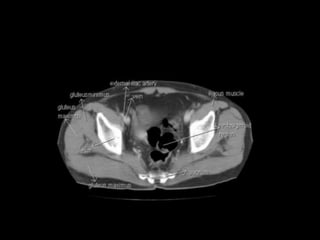

Cross section anatomy of abdominal ct scan

Cross section anatomyof abdominal ct scan